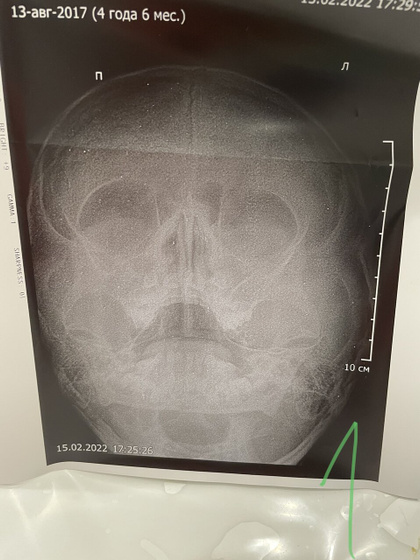

Двусторонний риносинусит у обоих, у младшего + бронхит. У меня двусторонний полисинусит (D<S), ринит. А началось всё с меня 2,5 недели назад, писала тут что с 6 утра 38,3, днём до 39. КТ, анализы кровь моча биохимия в норме относительно, узи почек в норме — из-за чего темп непонятно. Через два дня в воскресенье закладывает нос, напрочь. И вот пошла третья неделя моего заложенного носа, местами дышу как рыбка ртом хватая воздух. У старшего нос забился как и у меня где-то с неделю. У младшего непонятно, но тоже немного сопли, начал покашливать. По итогу, вчера съездили на рентген в детскую поликлинику, я тоже напросилась (ибо к Лору времени, желания и сил у меня нет идти). Итог на фото и в тексте.